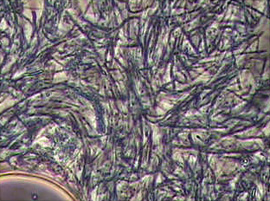

当院では、「ジスロマック」と呼ばれる抗菌薬を用いて歯周病菌の殺菌を行っています。下記の画像は、治療前と治療後の口腔内を特殊な顕微鏡で撮影し比較したものです。投薬後には歯周病菌の数が大幅に減少していることが確認できます。

従来の機械的な歯石除去だけでは除去しきれない深部の汚れや、歯周ポケット内の細菌叢(フローラ)をコントロールするために、薬剤との相乗効果が期待できます。この治療法は、外科手術を回避できる場合があるなどのメリットがある一方で、患者さん個々の歯周ポケットの深さや歯肉の状態によっては適応が限られるケースもあります。

そのため、当院では診断結果を踏まえて最適な治療手段を提案し、痛みやダウンタイムを最小限に抑えながら症状の改善を図っています。薬剤を用いた局所的な殺菌アプローチと組み合わせることで、再発率を下げ、治療効果の持続を目指しています。